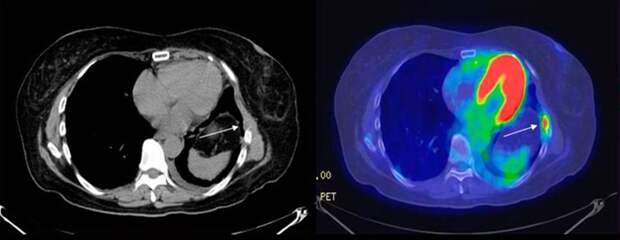

С января по октябрь жители Нижегородской области прошли 5861 бесплатных высокоточных диагностических процедур ПЭТ-КТ. Об этом сообщил главред «Стационар-пресс» Алексей Никонов. Процедура ПЭТ-КТ используется для выявления онкологических и неврологических заболеваний, а также патологий сердца. Она позволяет выявить злокачественные новообразования на ранней стадии, определить размеры и область её распространения.

Обследование проводится бесплатно по ОМС, но пока что только в соседних регионах. Нижегородская область выделила на проведение ПЭТ-КТ более 200 млн рублей. С начала года процедуру прошли 5861 жителей региона.